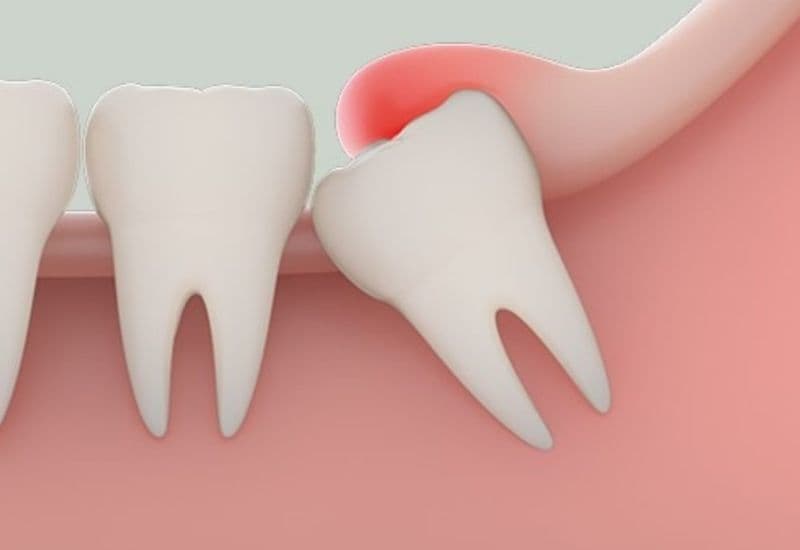

2.1. Răng khôn mọc lệch, mọc ngầm – Nguyên nhân phổ biến của tình trạng sưng nướu răng khôn

Răng khôn (răng số 8) là răng mọc sau cùng trong cung hàm, thường xuất hiện ở độ tuổi từ 17–25. Tuy nhiên, do không còn đủ khoảng trống để mọc bình thường, răng khôn rất dễ mọc lệch, mọc nghiêng vào răng bên cạnh hoặc mọc ngầm trong nướu. Khi mọc sai hướng, răng khôn có thể gây áp lực lên mô mềm và các răng lân cận, khiến vùng nướu bị chèn ép, tổn thương hoặc rách nướu. Điều này làm xuất hiện triệu chứng sưng tấy, đỏ nướu và đau nhức kéo dài. Trường hợp nghiêm trọng có thể dẫn đến viêm nhiễm hoặc u nang quanh răng khôn.